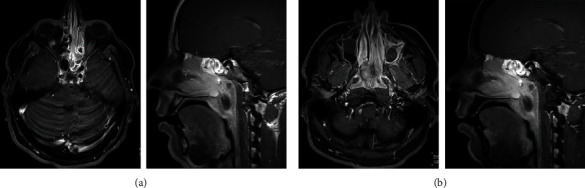

Sarcoma with BCOR genetic alteration is an exceptionally rare and emerging subtype of sarcoma. It is categorized into two types: BCOR-related gene fusions such as BCOR::CCNB3 sarcomas and other BCOR-rearranged sarcoma and sarcomas with internal tandem duplication of BCOR genes such as infantile undifferentiated round cell sarcomas and primitive myxoid mesenchymal tumors of infancy. BCOR::CCNB3 sarcomas predominantly arise in bone rather than soft tissue and exhibit a higher occurrence in children and adolescent males, whereas sarcomas with BCOR internal tandem duplication show a wider age range but usually arise in the first year of life. Due to their rarity, there is ongoing debate and uncertainty regarding the best treatment approach, with a lack of specific clinical trials addressing these tumors. In this report, we present a unique case of sarcoma with internal tandem duplication of BCOR gene originating in the nasal region. The tumor was successfully and completely resected using the standard VDC-IE chemotherapy protocol, resulting in an unprecedented 100 percent tumor necrosis. The patient has completed the protocol and remains recurrence-free 13 months after diagnosis. This case suggests potential efficacy of the standard VDC-IE protocol in achieving remarkable responses in BCOR rearrangement sarcomas, including the internal tandem duplication subtype. However, further studies are needed to determine the optimal treatment strategies for this disease.